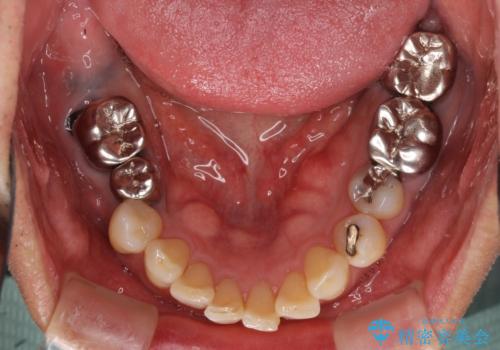

- 奥歯の欠損部へのインプラント治療を希望して来院された患者様です。

抜歯をしてから長年経過しており、レントゲンからは十分に骨があることが分かっていたため、速やかに治療を開始することとしました。

インプラント治療に当たり、手前の銀歯2本の審美回復も希望されたため、3歯のオールセラミッククラウンによる補綴治療を行うこととしました。